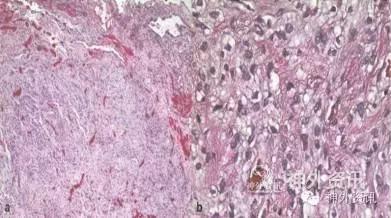

结合临床和影像学表现,初步诊断为脑室内脑膜瘤。经胼胝体入路开颅手术,切开胼胝体后,可见左侧脑室壁附着质地软、橡胶样的灰红色肿瘤,将肿瘤完全切除。病理学检查报告为平滑肌瘤伴上皮样变(图2)。免疫组化(ICH)染色结果显示肌动蛋白(SMA)、结蛋白表达阳性;Masson三色染色显示肿瘤组织纤维排列疏松,支持平滑肌分化。该组织上皮细胞膜抗原、孕激素受体(PR)、胶质纤维酸性蛋白(GFAP)、神经丝蛋白(NF)、S100、突触素、CD34、黑色素瘤抗原(Melan A)、人黑色素瘤45染色均阴性。荧光原位杂交(FISH)示EB病毒阴性。

图2. 显微镜下肿瘤组织HE染色结果。a.低倍镜下可见肿瘤周围血管和粘液样表现;b.高倍镜下见梭形细胞核,罕见有丝分裂。